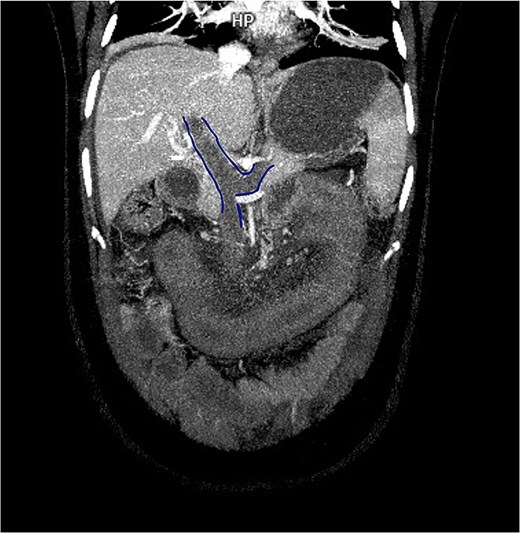

Contrast-enhanced computed tomography (CT) demonstrated thrombosis of the portal vein, splenic vein, and superior mesenteric vein with proximal dilatation, diffuse jejunal thickening, mesenteric fat stranding, and mild splenomegaly (Figs 1 and 2). No pneumatosis or portal venous gas was seen.

Contrast-enhanced CT in venous phase showing thrombosis of the portal, splenic, and superior mesenteric veins with proximal dilatation and thickening of the jejunal wall.